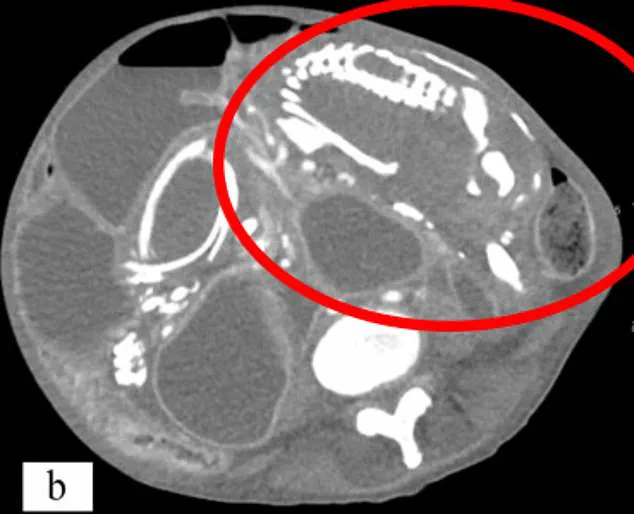

Ectopic pregnancies occur in approximately 1 in 11,000 pregnancies, according to Dr. Lee. The uterus is uniquely designed to accommodate a growing foetus, but when an embryo implants elsewhere, such as the fallopian tubes, ovaries, or abdominal cavity, the risks escalate. If the pregnancy fails before 12 weeks, the body can reabsorb the cartilage-based skeleton. However, if the foetus survives beyond this point, the skeletal system shifts to bone, which the body cannot reabsorb. The immune system then encases the dead foetus in calcium, creating a protective, calcified mass that can remain in the body for decades.

This process, akin to mummification, can leave the lithopedion asymptomatic for years. However, complications may arise when the mass presses on surrounding organs, causing chronic pain, urinary issues, or bowel obstructions. Infections can also develop, leading to abscesses or, in severe cases, life-threatening conditions. Dr. Lee emphasized that while lithopedions are rare, they are more likely to occur in populations with limited access to prenatal care, cultural barriers to medical treatment, or socioeconomic challenges.

A tragic example from 2023 involved a 50-year-old woman from the Congo who carried a lithopedion for nearly nine years. She arrived in New York complaining of stomach cramps and a gurgling sensation after eating. Scans revealed the calcified foetus had been compressed by her intestines for years, a result of a miscarriage she had not recognized. Despite medical intervention, she refused treatment, believing her symptoms were caused by a curse. She died 14 months later from malnutrition and complications caused by the mass.